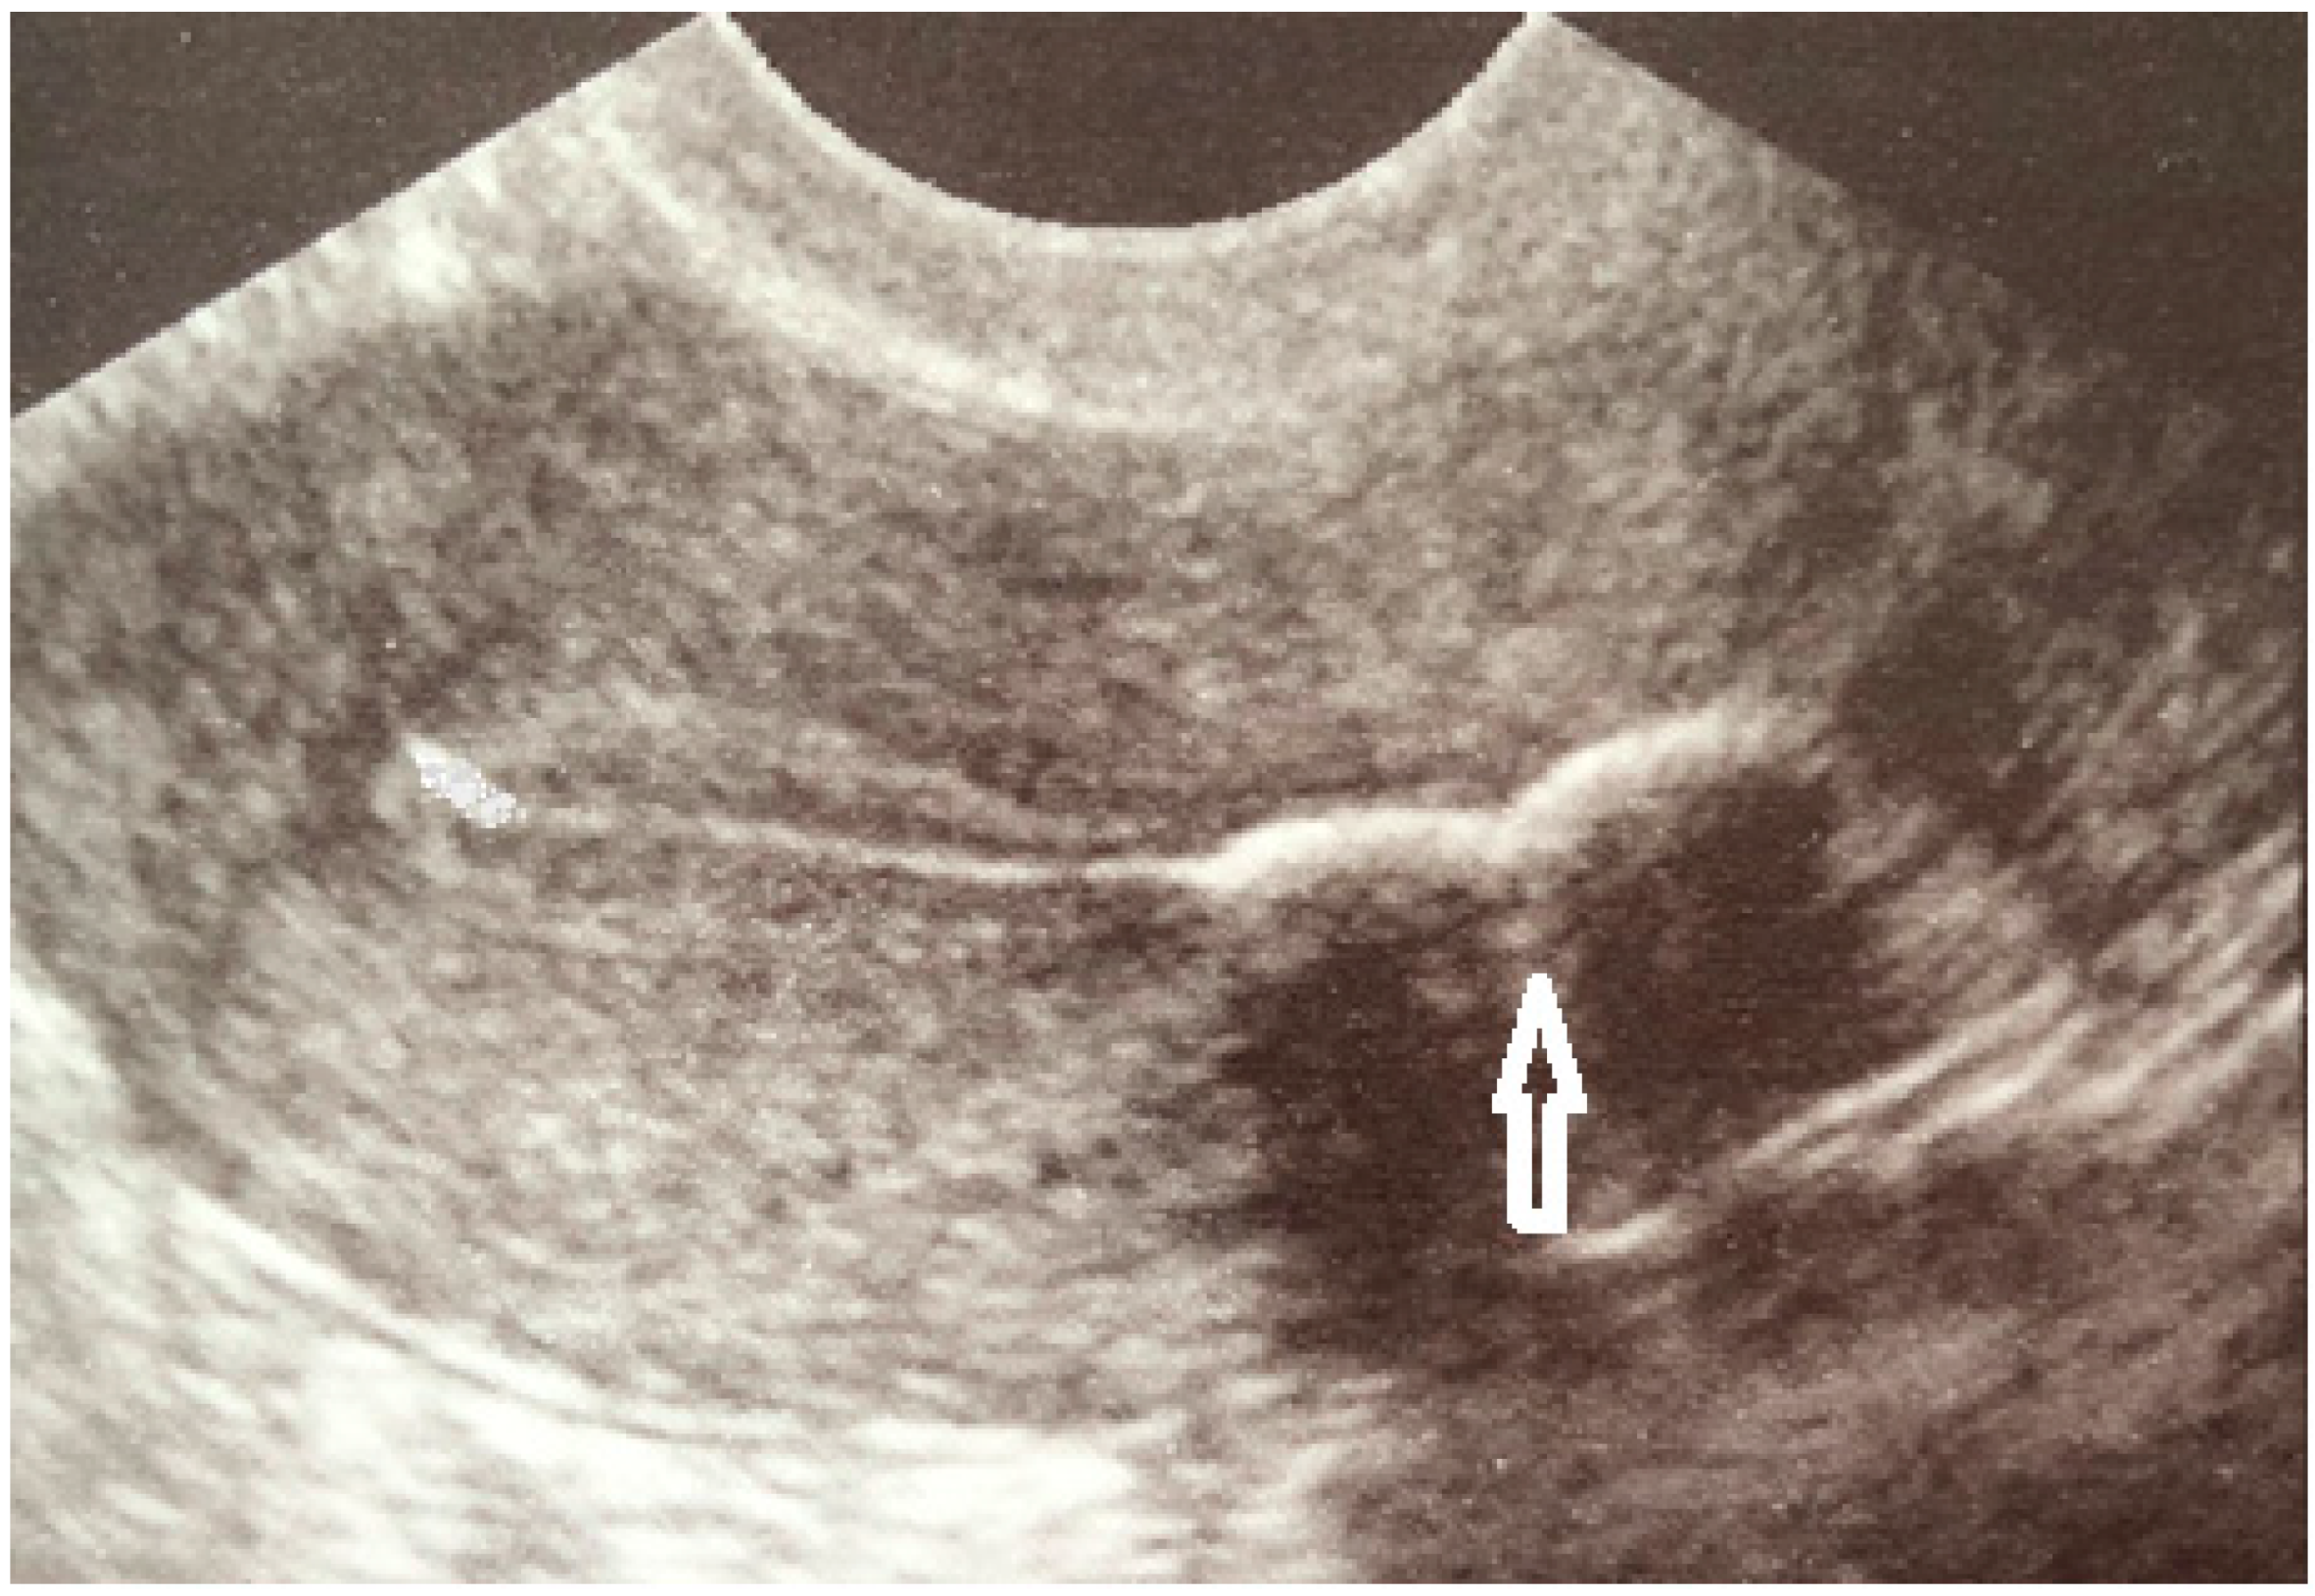

Case Report

- Grigore, M.; Pristavu, A.; Gafitanu, D. Ultrasound features of osseous metaplasia of the endometrium: Case series and review of the literature. Clin. Imaging 2018, 52, 260–263. [Google Scholar] [CrossRef] [PubMed]